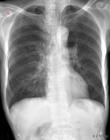

就诊科室:中医科 中医综合易感人群:无特发人群需做检查:胸部平片 肺功能检查 肺部检查 肺和胸膜叩诊 肺和胸膜视诊 肺和胸膜听诊常用药物:沙美特罗替卡松气雾剂 转移因子胶囊 丙酸倍氯米松气雾剂 复方菠萝蛋白酶肠溶片 头孢氨苄胶囊 氨茶碱片 脾氨肽口服冻干粉 多索茶碱葡萄糖注射液 氨茶碱注射液 注射用过氧化碳酰胺 注射用盐酸溴己新 固肾定喘丸 茶碱葡萄糖注射液 盐酸溴己新片 寒喘祖帕颗粒 注射用氨茶碱 醋酸地塞米松片 益心巴迪然吉布亚颗粒 茶新那敏片典型症状:喘息 烦热 口干渴难忍 面色苍白 痰鸣音传染方式:无传染性治疗方式:无传染性相关疾病:哮喘 喘证